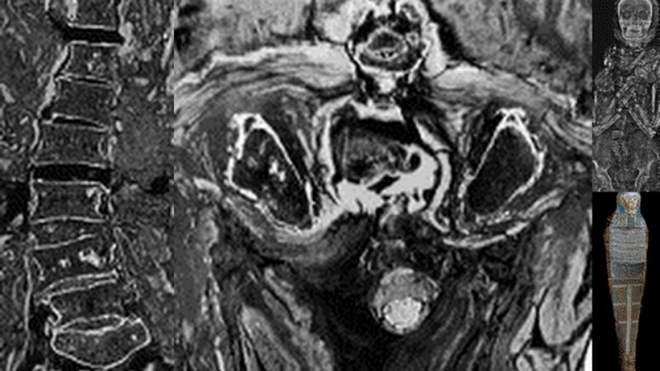

在埃及的木乃伊的研究为例,研究人员没有发现癌症的迹象,除了一个案例外。从埃及木乃伊的组织碎片进行水化和置于显微镜下观察。研究人员发现在木乃伊的癌症中只有一个案例。

自然杂志的癌症评鉴报告,癌症的化石证据不实,科学文献提供几十个,大多是有争议的,在动物化石的例子。即使是数以千计的尼安德特人骨骼的研究中也只有一例癌症的可能性。